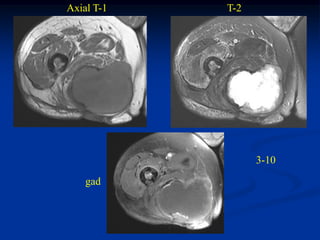

Case #1180                    Axial T-2 MRI

26 year male with fibrosarcoma calf

Case # 1181                 Sagittal T-1 MRI

51 year female with fibrosarcoma ankle

Case #1180 Axial T-2 MRI 26 year male with fibrosarcoma calf

Case # 1181 Sagittal T-1 MRI 51 year female with fibrosarcoma ankle